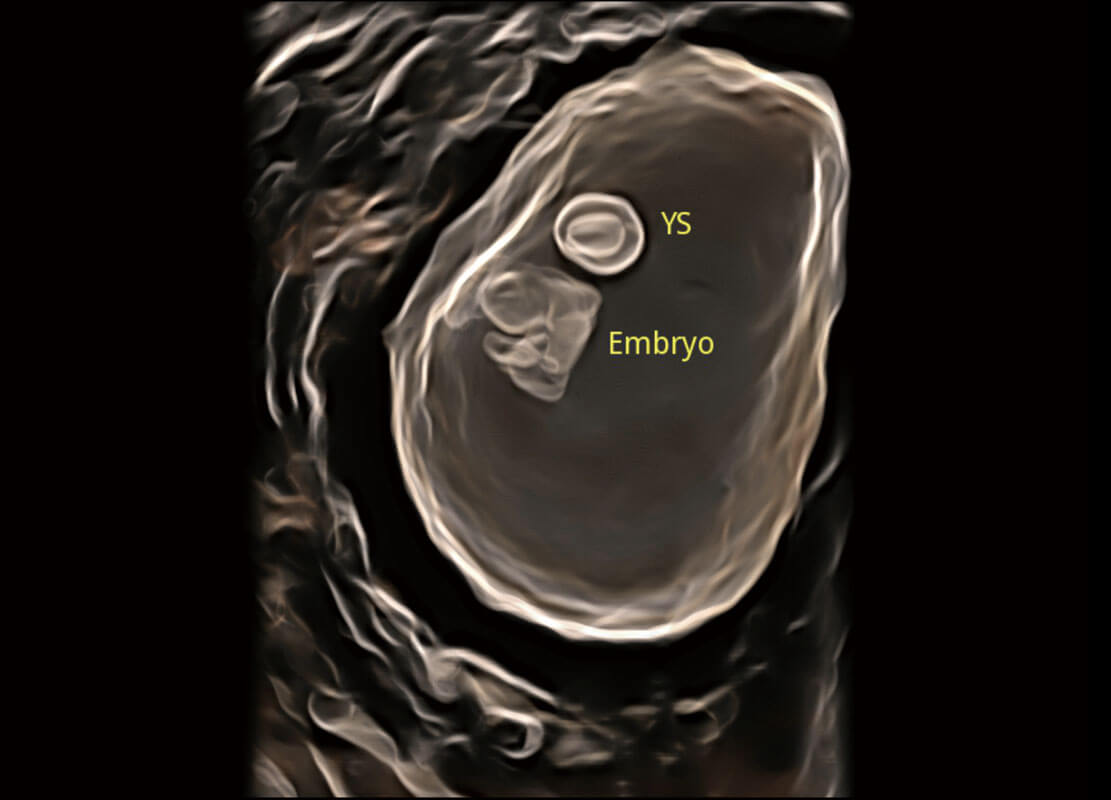

早孕筛查

P60在胎儿早孕期超声筛查中为您带来优异的图像质量。

• 高分辨率容积成像-早孕胎儿

• 光影成像-孕囊